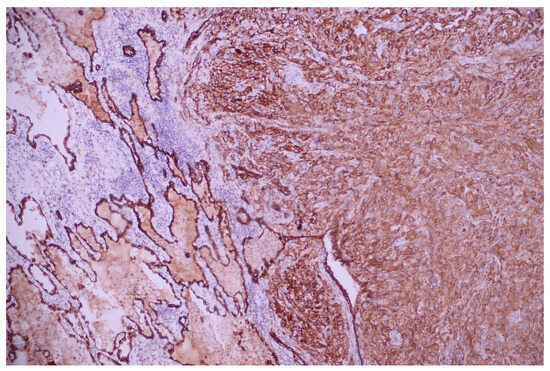

3.1. Case No. 1

3.2. Case No. 2

3.3. Case No. 3

3.4. Case No. 4